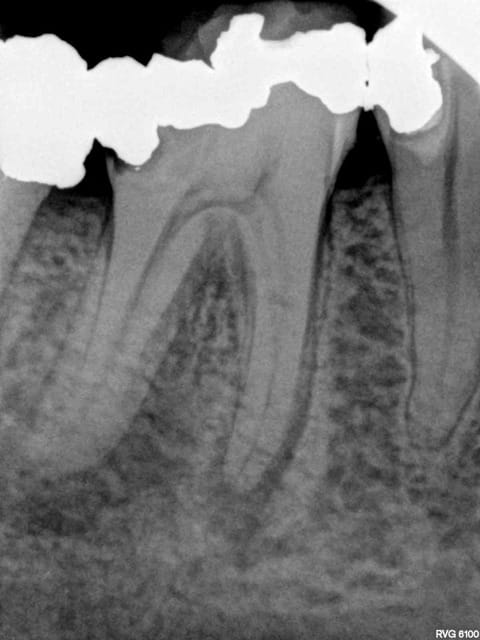

J'y travaille pour trouver un moyen simple et efficace pour poser la digue dans toutes les situations comme celle ci dessous. Tiens c'est tout frais, endo sc33 en 1 temps, 1H 15 et encore je n'ai pas d'assistante au fauteuil.

Technique "Monocône"....C'est un peu "has been" je trouve.... ;-)

Pulpite indication endo. perte de substance: Indication onlay , mais pas dans le panier de soins donc sc 33, couronne coulée : patiente CMU.

Dis donc chicot t'es peut être le roi de l'endo mais au niveau économie tissulaire , ouverture de chambre , tu utilises un black et decker comme contre angle ?... t'y vas pas de main morte ... t'aurais peut être pu éviter le tenon alors , et qui sait la couronne .... et puis un genre screw post titane ? avec un matériau plastique perso je trouve pas ça terrible ... mais je ne suis qu'une petite dentiste qui utilise encore l'amalgame ... houuuu la méchante .....bon et puis la (ou le ) mitrailler comme ça pendant le soin juste pour nous montrer , faut pas tu sais , tu perds un temps fou ... après le temps de poster tout ça ..... t'imagines le temps perdu pour la rentabilité du cabinet ....

Surtout mono-cone sans ciment. mais c'est vrai que quand on ne fait pas d'essayage de cones on ne risque pas de voir pas la différence.-))))

Mais je ne me cache pas que je les scelle de temps en temps. Mais manque de bol pas là. Thermo compactés au mac spaden. Tu vois peut être la différence non ?